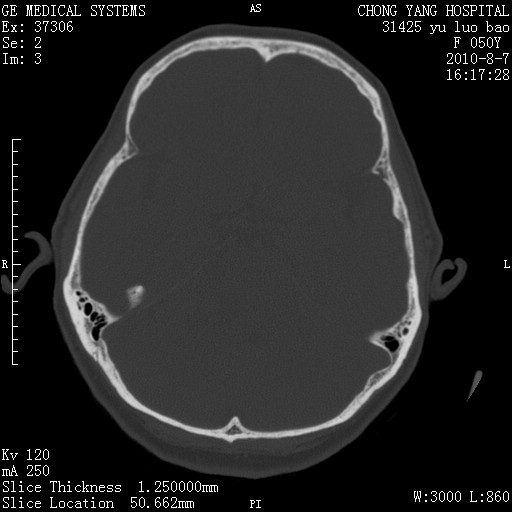

标题: CT28285:听力下降一年,头昏。 [打印本页]

标题: CT28285:听力下降一年,头昏。

骨窗示右侧内听道扩大,考虑右侧听神经瘤。